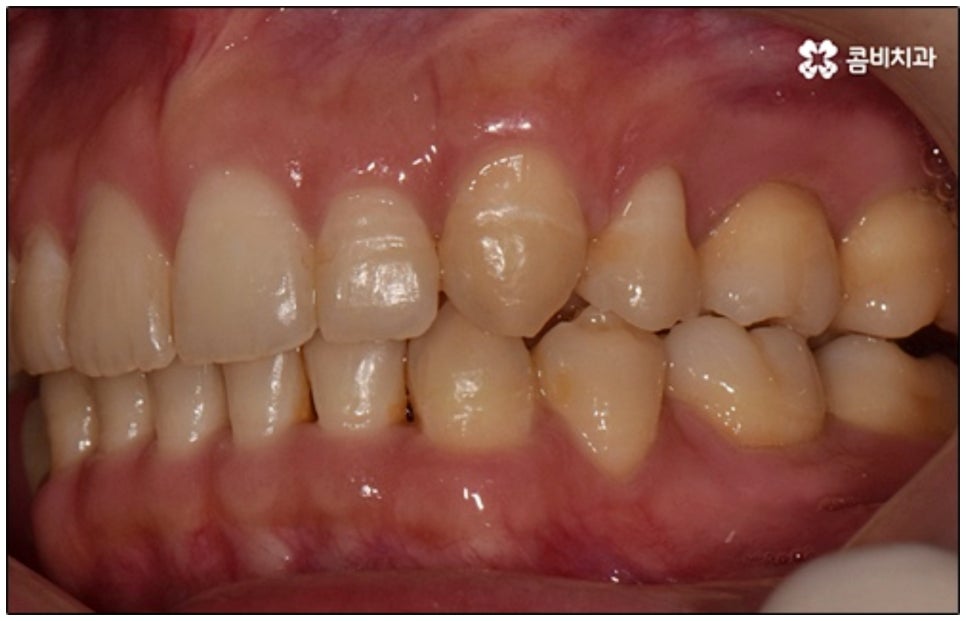

말씀드린 것과 같은 다양한 이점들이 있기 때문에 현재 본원의 교정 환자분들은 대부분 클리피씨교정 장치를 이용하여 치료를 진행하고 있습니다. 사진 역시 돌출입 교정을 위해 발치 후 클리피씨교정 장치를 이용하신 환자분의 케이스인데 시간이 지날수록 점차 앞니가 자연스럽게 들어가고 위아래 교합이 정확하게 맞아가는 것을 확인하실 수 있을 거예요.